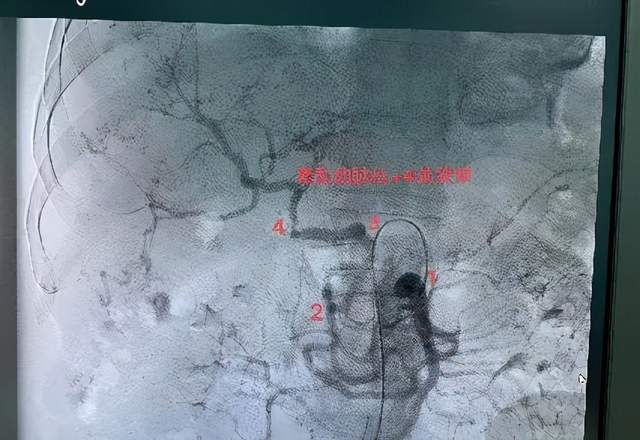

原发性肝癌血管介入

直肠癌出血栓塞

乳腺癌破溃出血

血管畸形、脾动脉破裂、肠道出血等栓塞